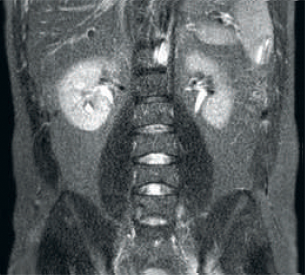

Result: Improved SNR and image resolution

Result: Noisy images using identical scan parameters

dStream RF receive technology digitizes the MR signal directly in the RF coil, resulting in an increase of up to 40% more SNR* throughout the whole image volume.